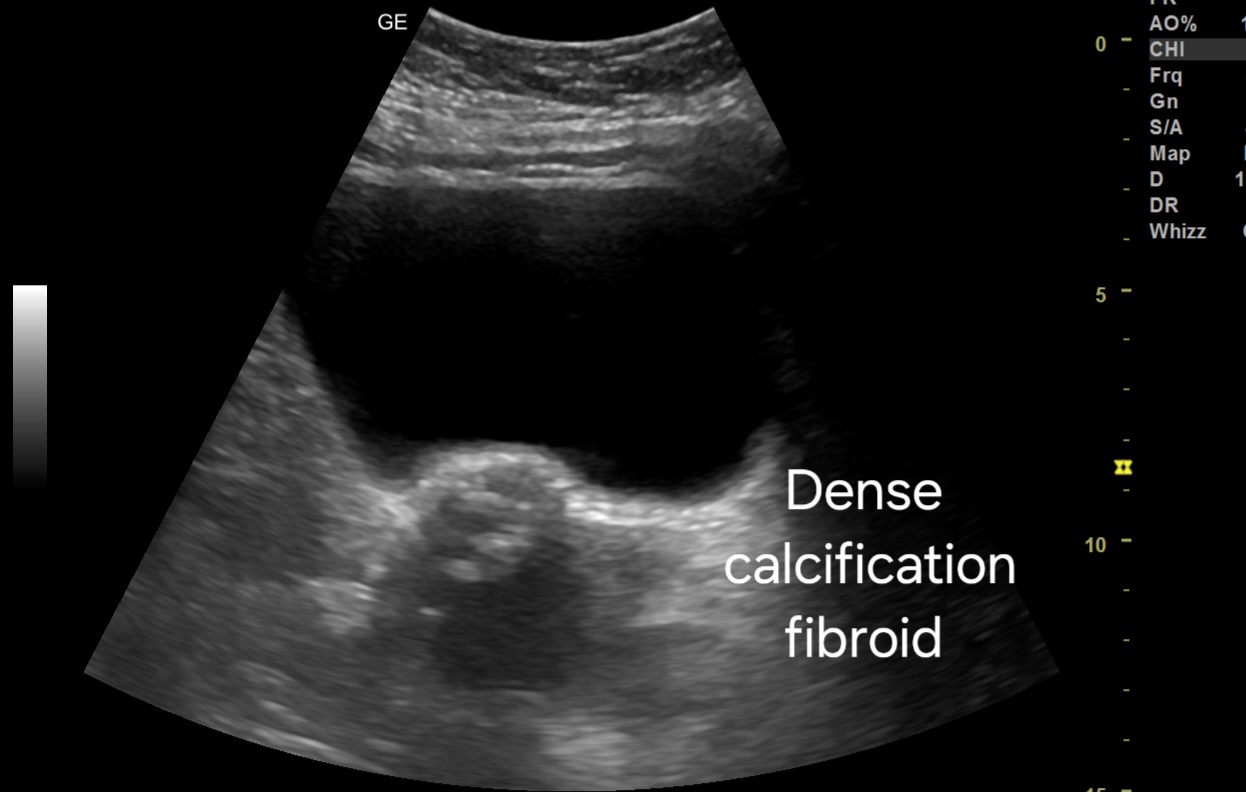

- Transabdominal Scan:

- Small fibroid located in the uterine wall.

- Severe calcification evident within the fibroid, causing acoustic shadowing.

- Hyperechoic appearance due to calcification, with reduced vascularity.